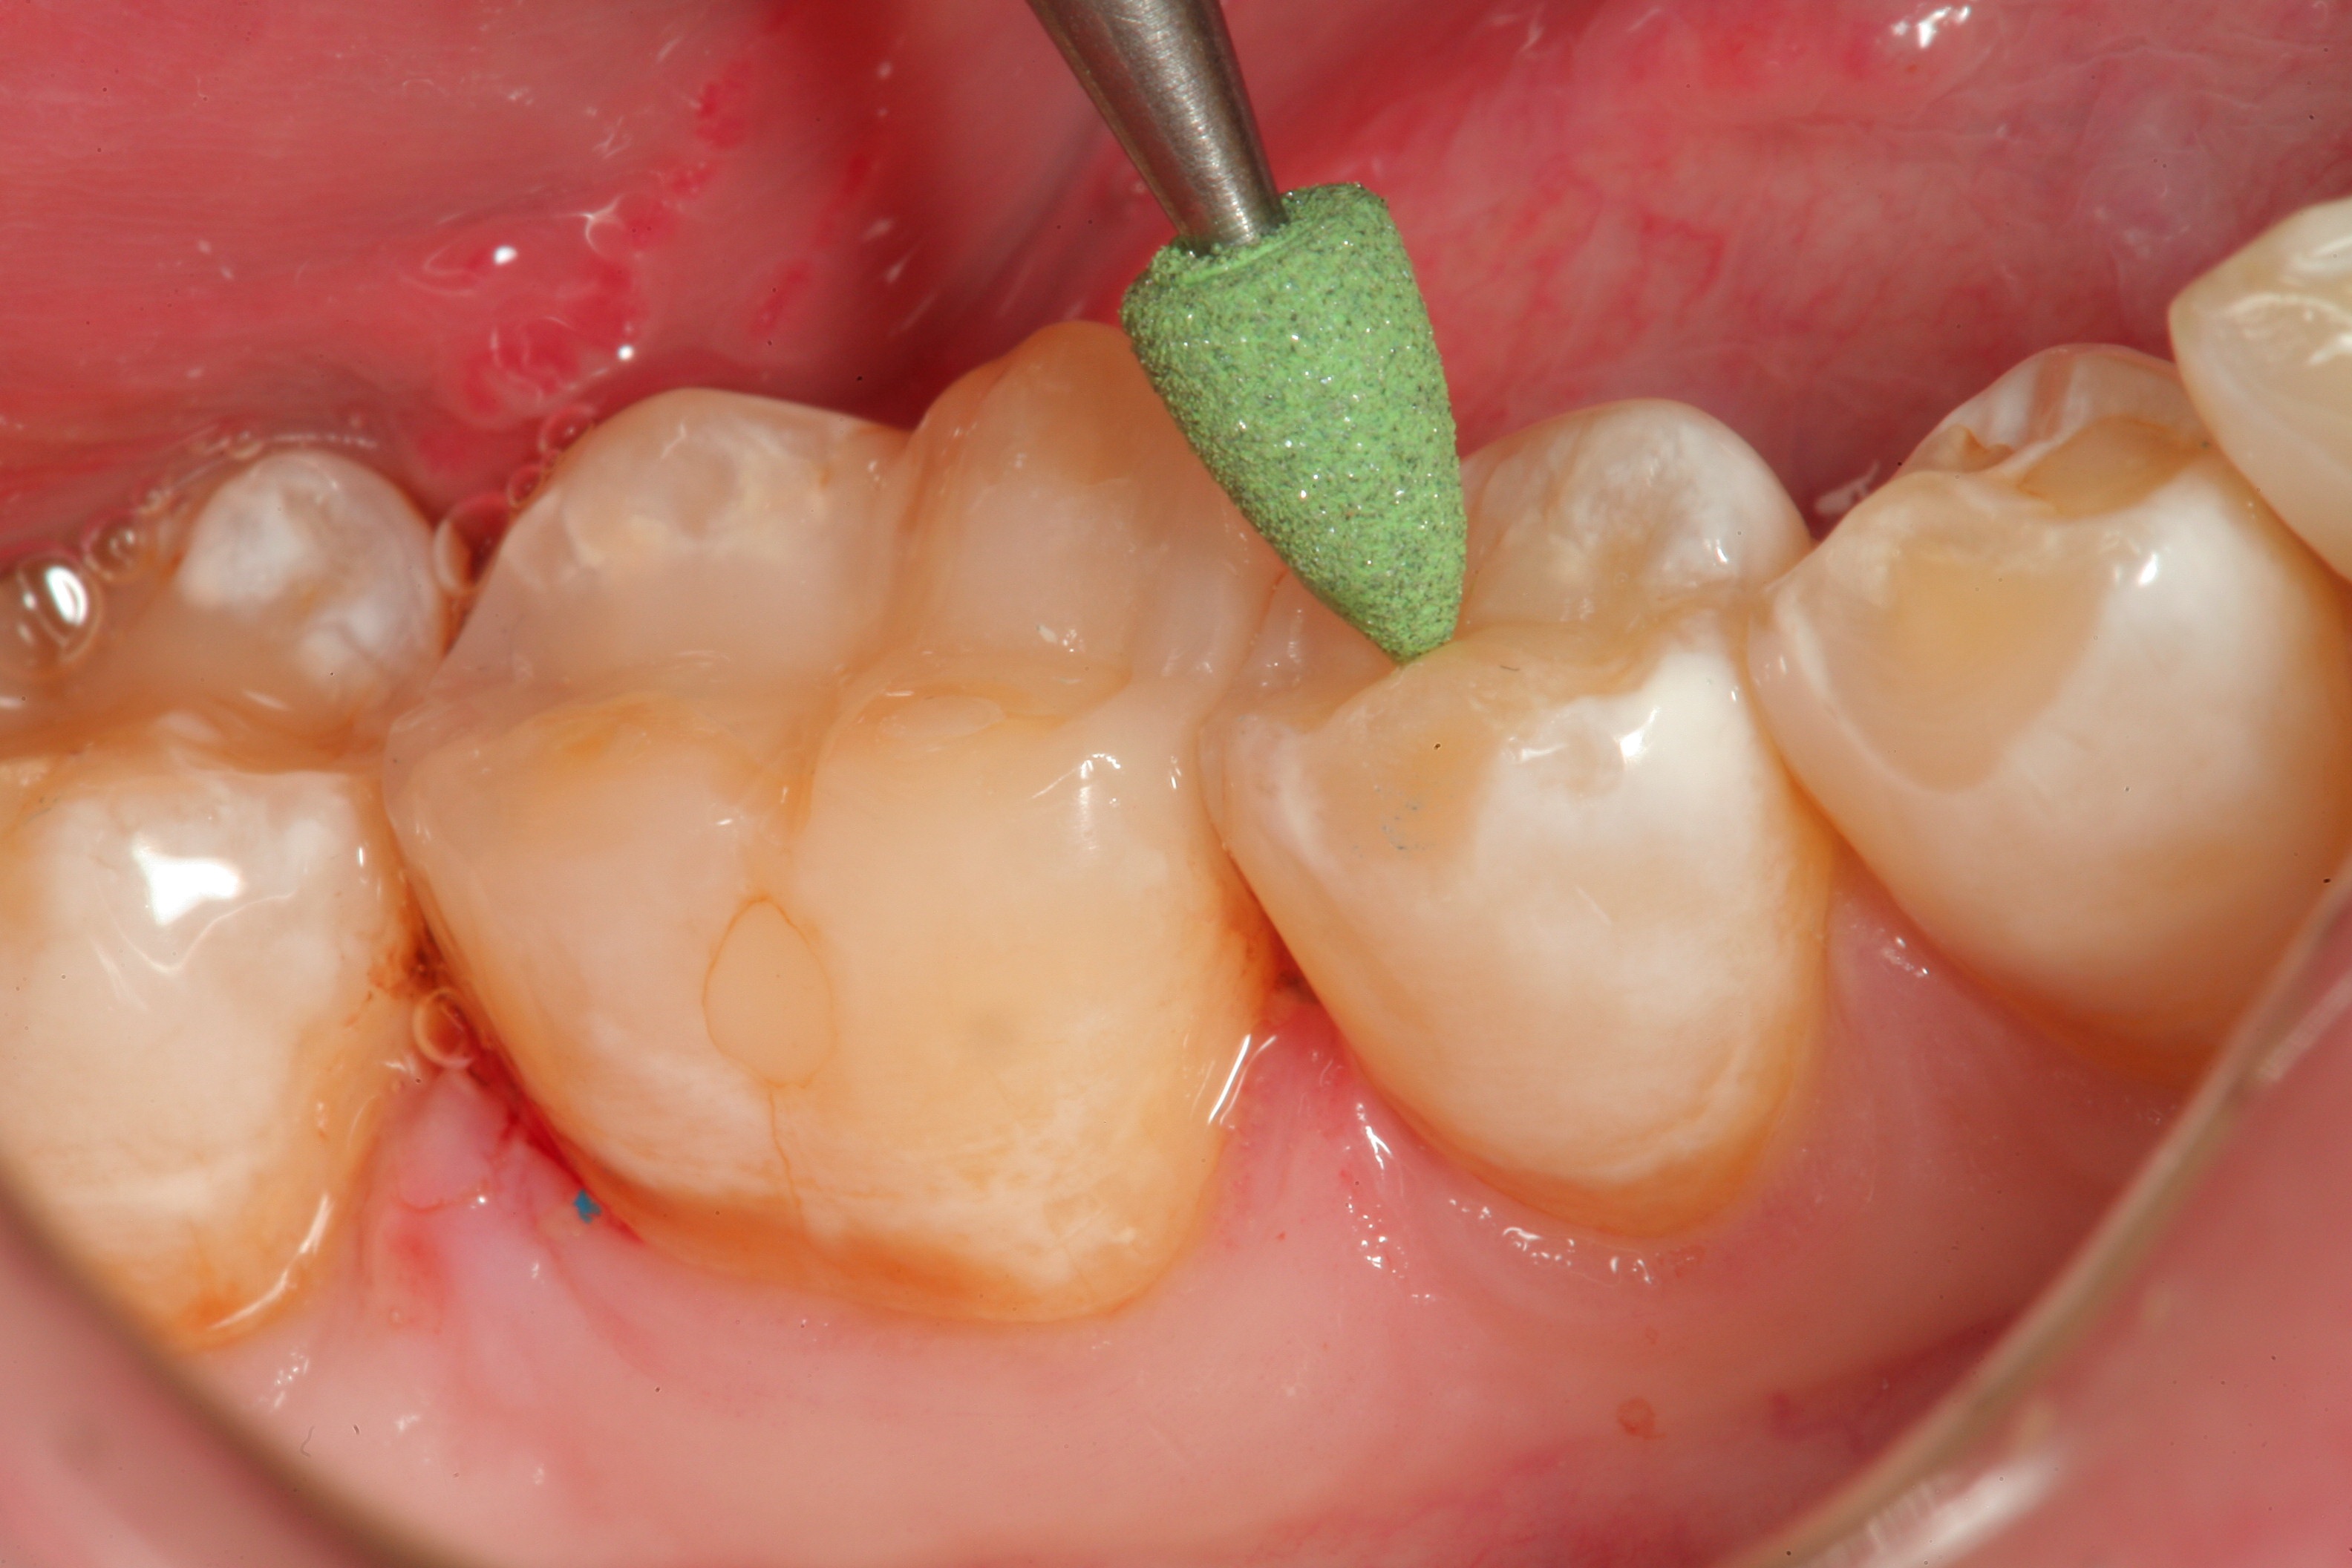

Fig 5. A rubber polishing wheel is used to get into the occlusal anatomy of the restorative material and create a highly polished surface to the restoration.

Figure 5